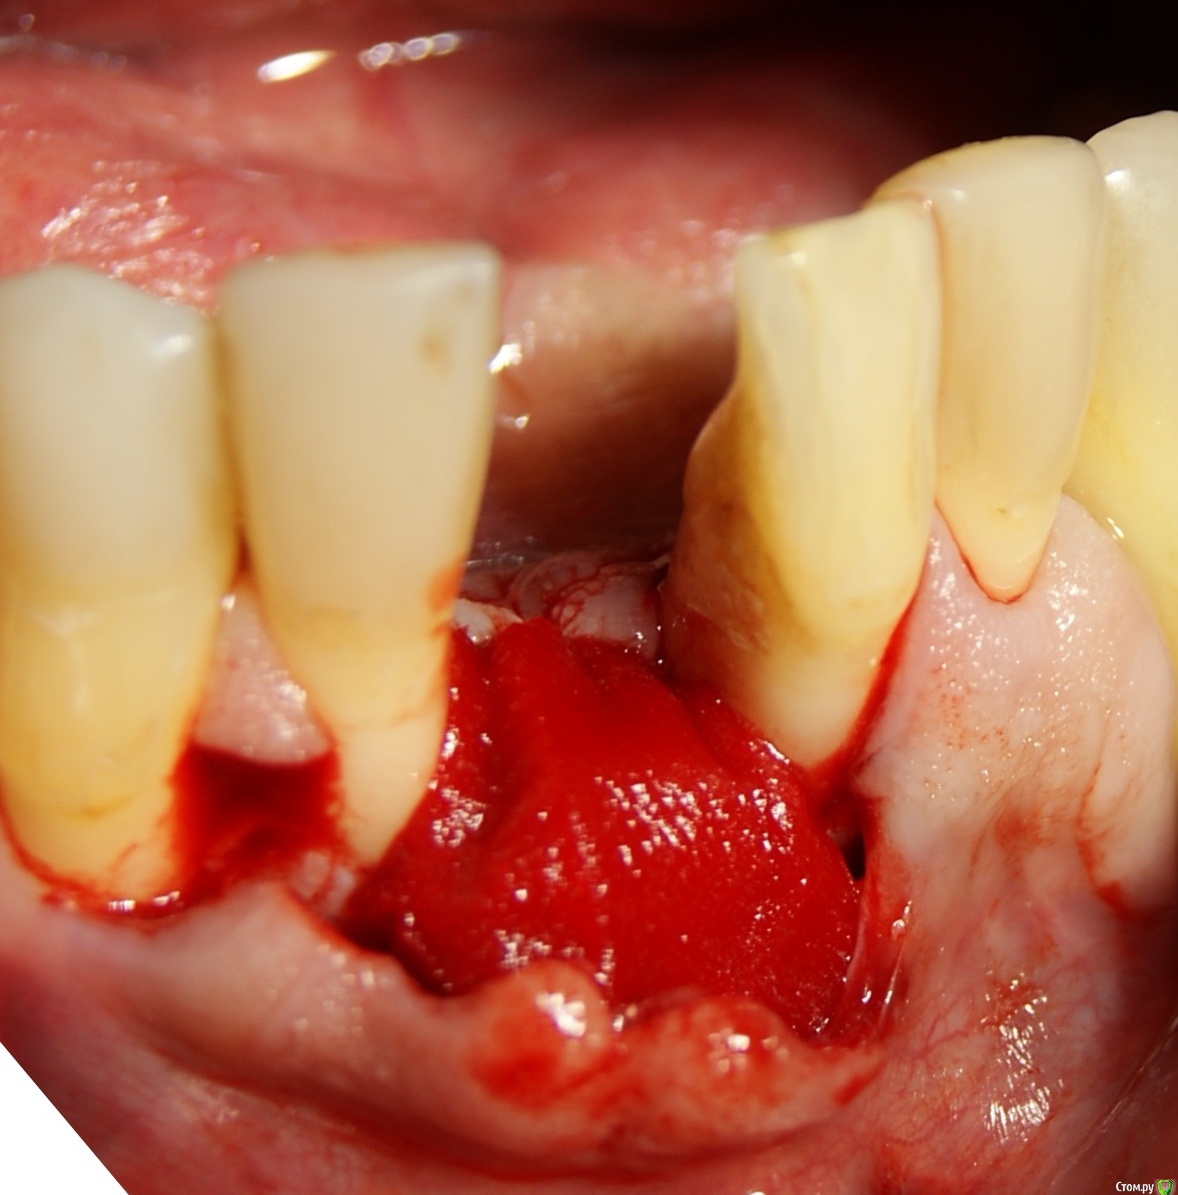

Jurai Опубликовано 25 декабря, 2016 Поделиться Опубликовано 25 декабря, 2016 *Предупреждение: фото на "мыльницу", не все этапы удались, но я работаю над этим) Вот пациент. Приятнейший, во всех отношениях, с негативным отношениям к мостовидным конструкциям. Полтора года лечил 41з по поводу периодонтита: толку не вышло. Удалил у широко известного многим стоматологам, особенно выпускам последних годов, доктора с ученой степенью. После удаления 4 месяца, по КТ область вполне достойно выглядит. Вот с чем пришел, обычное дело, все прилично: Раскрываю, а там между тонкими кортикалками мягко и упруго - резидуальная, фото нет. Открываю сильнее чем обычно, с расстройства не особо удачно. Кюретаж : Вид после, ушла вестибулярная кортикальная вместе с кистой: Сверлим 2,0, позиционердля рентген-контроля Имплантат ADIN UNP2,75Х11,5мм Ауто, джейсон коллагенфлис (что было под рукой) Швы. Контроль, перещелкивать не стали. В общем, понравился имплантат, для себя пометку кюретажить тщательнее, не надеяться, что организм все переварит. 1 9 Ссылка на комментарий